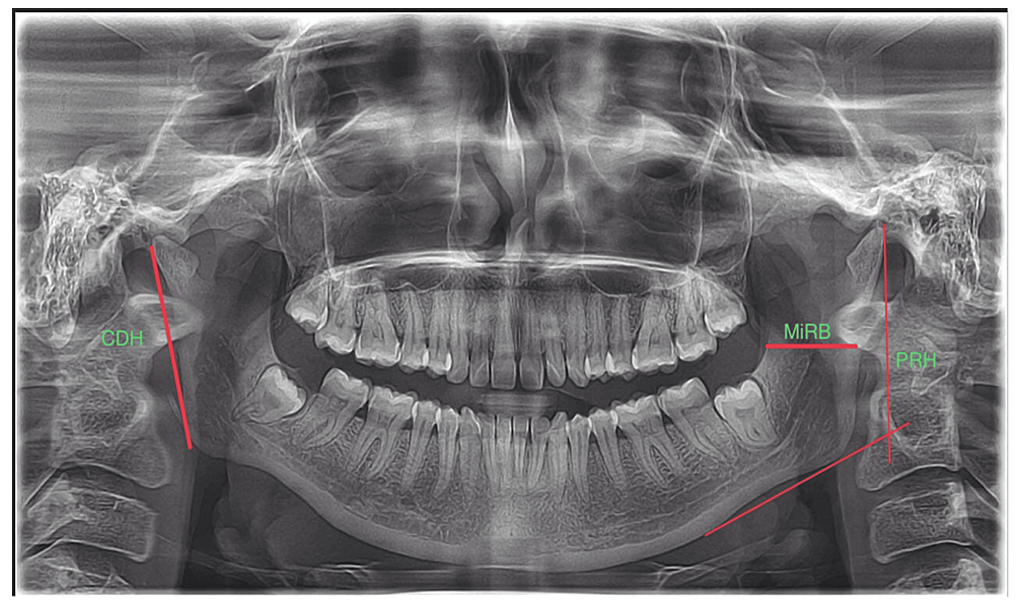

3D OPG

A panoramic radiograph is a panoramic scanning dental X-ray of the upper and lower jaw. It shows a two-dimensional view of a half-circle from ear to ear.

Mandible / Maxilla

This scan provides full madible evaluation for diganosis and teatment planning for any problem related to mandible, like fracture, cyst, nerve study, imacted tooth,